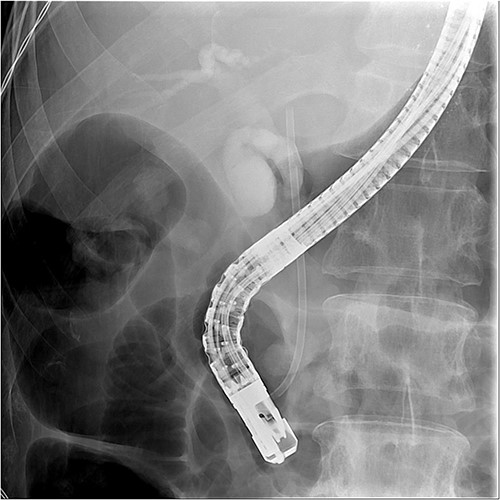

And then, a 7 French bostone scientific plastic stent was inserted over the guide wire for bile diversion. However, hemobilia was noted to be draining out from the stent right after. After reviewing the image, we realised that PVC was probably made (Fig. 3). After discussing with the general surgeon, we decided to arrange immediate surgical exploration to check for collateral damage and remove the CBD stones for cholangitis resolution. The stent was thus left inside for surgical guidance. Before the surgery, abdomen computed tomography (CT) was done and revealed retained contrast medium in the bile duct (Fig. 4) and malposition of the CBD internal stent with upper portion in the main portal vein (Fig. 5).

Fluoroscopy image showed the plastic stent penetrated through the CBD.